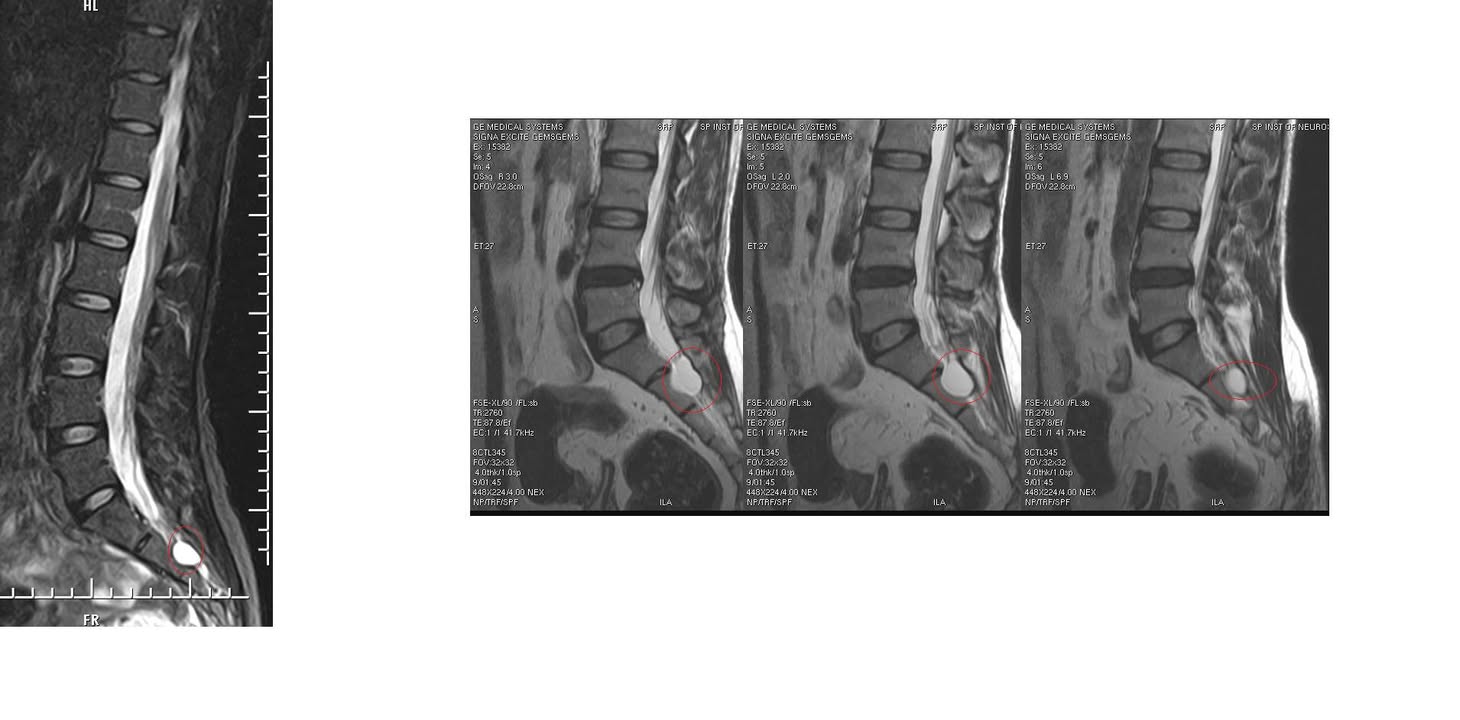

Cervical Spine Treatment Cases 腰椎治療案例 #今天來聊巨大骨刺為何可以吸收回去! #椎間盤突出需要多久才能吸收呢? #馬尾神經症候... 2020.09.08 #典型假性坐骨神經痛 #原來是梨狀肌症候群 #核磁共振排除椎間盤突出 #抽絲剝繭真相大... 2020.08.13 #嚴重椎管狹窄醫案 #感謝台北林大哥熱情見證 #從寸步難行到輕快漫步 #鍛鍊多裂肌的重... 2020.08.12 #椎間盤突出可以吸收回去嗎 #微針治療原理是什麼 #何時一定要接受神外開刀 #一張圖秒... 2020.08.11 #感謝花蓮鄉親林大姐熱情見證 #一分鐘認識椎管狹窄 #原本痛到無法走路打算開刀了 #脊... 2020.08.01 #感謝新莊區林先生熱情見證 #椎間盤突出跟纖維環裂隙的關係 #纖維環破裂突出可以不... 2020.07.28 #逆轉勝又一發case #原本疼痛一年多想說一定要手術治療了 #八週治療後症狀全部消失 #... 2020.07.25 #巨大椎間盤突出一定要開刀嗎 #除了開刀以外的選擇 #感謝台北市吳先生熱情見證 2020.07.24 #腰椎滑脫的疼痛心酸誰人知啊 #一分鐘瞭解腰椎滑脫 #哪一種情況需要積極開刀 #要如何... 2020.07.21 #巨大椎間盤脫垂一定要開刀嗎? #感謝新店林先生熱情見證受訪 #西醫手術有那些選擇... 2020.07.02 #纖維環裂隙AnnularFssures #MRI看起來不嚴重卻嚴重困擾患者 #感謝桃園市蕭先生熱情見... 2020.06.19 #骨刺有可能吸收回去嗎?? #疼痛超過六年的特殊案例探討 #MRI核磁共振前後對比 #感謝... 2020.06.14 #坐骨神經痛一定要開刀嗎 #突出的骨刺真的可以自己吸收嗎 #最新英國醫學期刊BMJ的看... 2020.05.30 #骨刺跟突出髓核有可能吸收回去嗎?? #特殊案例探討 #核磁共振一年後對比 2020.05.29 #從醫以來第一次碰到薦椎Tarlov cyst囊腫#左邊紅色圈圈是個案,右邊是國外案例#腰... 2020.05.23 ← 上一頁 10 11 12 13 14 下一頁 →